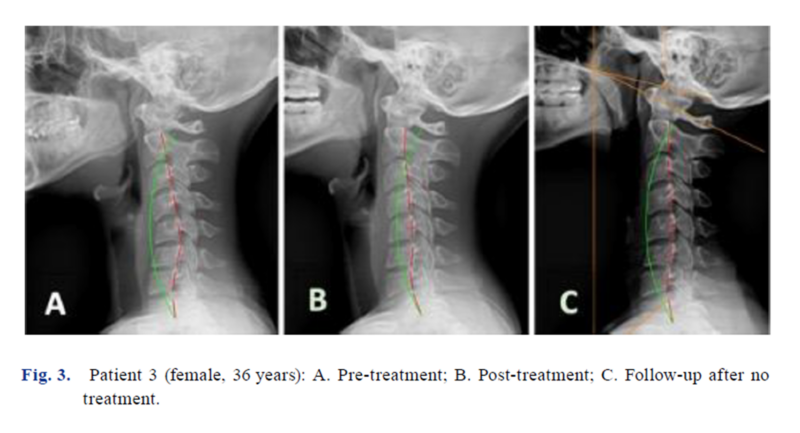

One of the most critical aspects of this study was the long-term follow-up, ranging from 11.5 months to 3.7 years. The researchers found that in patients who did not continue with maintenance care, the spine naturally began to regress toward its old shape.

On average, patients lost about 10° of their corrected curve over several years without ongoing treatment. However, interestingly, symptoms did not immediately return. Pain scores remained low (1.2/10) and disability scores remained excellent (5.4%). This suggests a “lag time” between structural regression and the return of pain.

The study concludes that to prevent this regression, a maintenance schedule of approximately two treatments per month is likely necessary to preserve the optimal spinal structure for life.